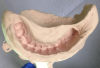

Figure 1: An example of a laboratory-made triple tray model with the finished crown on the abutment.

Figure 1